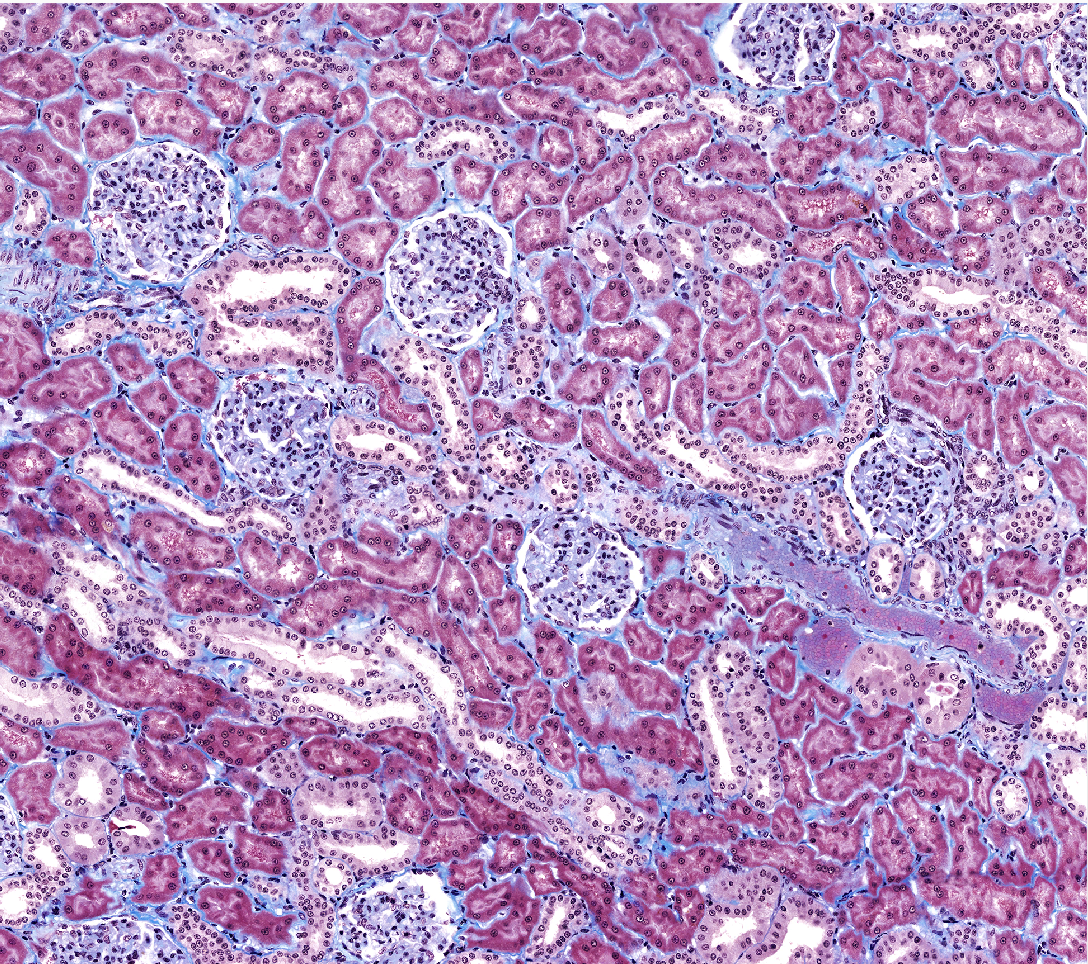

High magnification of renal cortex- list different parts